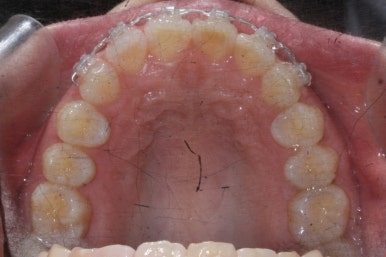

부산앞니교정 키다리아저씨치과에 처음 내원하셔쓸 당시의 입안 모습입니다.

앞니가 살짝 삐뚤어진 것을 볼 수 있고, 삐뚤어진 사이에서 약간의 틈새도 있었습니다.

예전에 치료 받으셨던 앞니 부분에 약간의 변색도 와서 미적으로 좋지 못한 상황이였습니다.